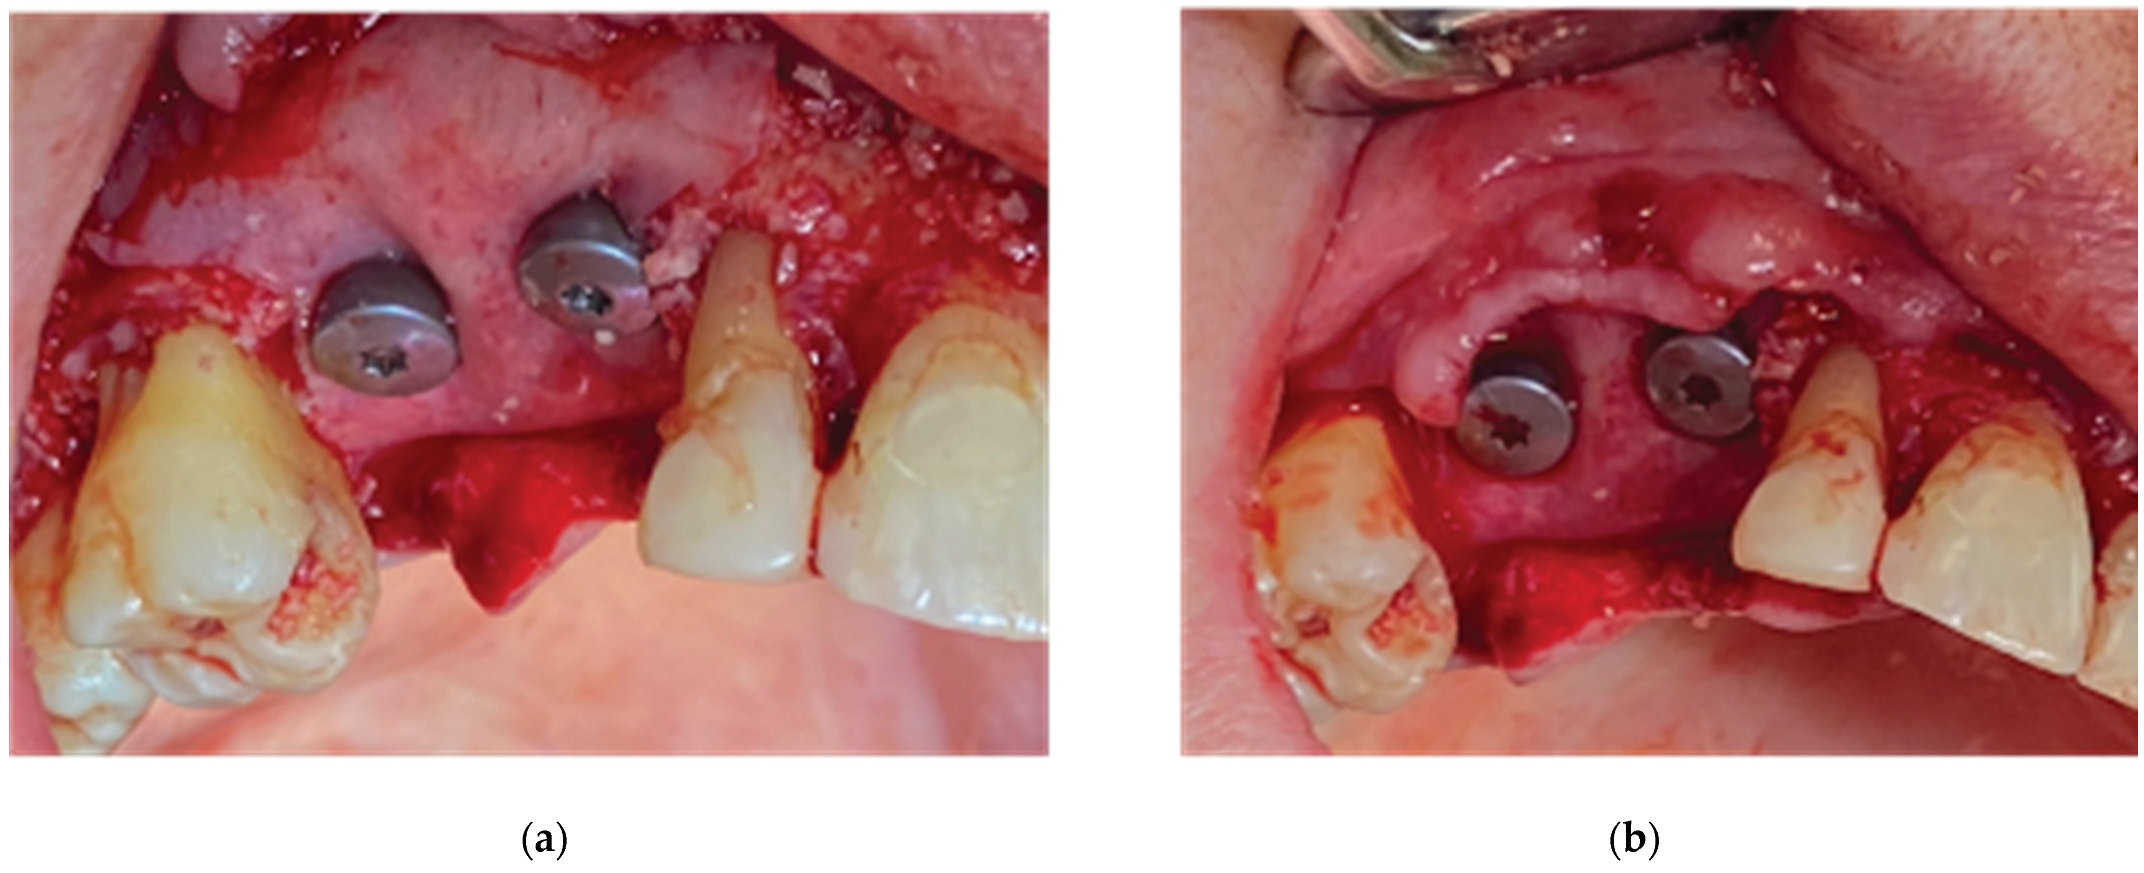

Figure 17. Stage 1 surgical procedure -(a) Initial Situation, (b) Incision design and extraction of 34 tooth, (c) Thin alveolar ridge after flap elevation, (d) Stock abutment-Lamina compound following over grafting.

A 68 year old female patient attended our clinic and requested a fixed solution for the posterior edentulous 35-36 area of quadrant 3. The patient was a healthy non-smoker without active periodontal disease (no attachment loss, pockets on probing and BoP). A pre-op Cone Beam Computed Tomography (CBCT) was performed on the lower third quadrant. The results revealed an important horizontal atrophy of the ridge at the area from the distal aspect of the 34 tooth element till the mesial aspect of 38 wisdom tooth. Bone density was defined as type 3 and the distance from the most coronal edge of the alveolar ridge to the inferior alveolar canal was enough to place dental implants (more than 10mm). Residual endodontic filling material within the bone structure was identified on area 36. A periapical lesion apically of 38 roots with underfilled root canal treatment and bone loss at the furcation area was also noted (Figure 16).

The clinical examination revealed a keratinised tissue width of 4mm upon a thin alveolar ridge, a mesioversion of the 38 element that additionally presented a type 2 mobility and a narrow class 3 furcation (Figure 17).

We decided that the short rooted element 34 should be extracted and replaced by a dental implant immediately after extraction along with a Poncho Lamina accelerated protocol for both 34 and 36 implant sites. As the 27 tooth was missing and the patient didn’t want to replace it, an implant rehabilitation for a future 3 unit bridge 34-36 was selected as the best treatment option. The Tooth 38 was left to be extracted at Stage 2 of the surgical procedure. In this particular case we used the same material as in case 1 but we added Everstick glass fibers to fabricate a provisional 3 unit fixture for cervical profile generation 34-36 during stage 2 procedure.

Stage 1:

Following local anesthesia (Articaine Hydrochloride / Adrenaline) the same surgical workflow was followed as in case 1: After flap elevation and release on both sides of the ridge, the tooth

element 34 was extracted and 2 Straumann SLA BLT 4.1 diameter implants (10mm length for the 34 implant and 8mm length for the 36) were placed subcrestaly with the Versah expansion protocol at a primary stability of 35N.cm. The site was overgrafted with 2 grams of Genos 0.5g and the trimmed Curved Cortical Lamina was secured above the implant platforms with healing abutments of 5mm diameter and 6mm height (StraumannGroup, Basel Switzerland) (Figure 17). Flap closure was achieved around the healing cups with the 2 suture layers and same suturing material described on Stage 1 and muscle pull reduction was achieved with a superficial incision on the depth of the vestibule as previously noted.